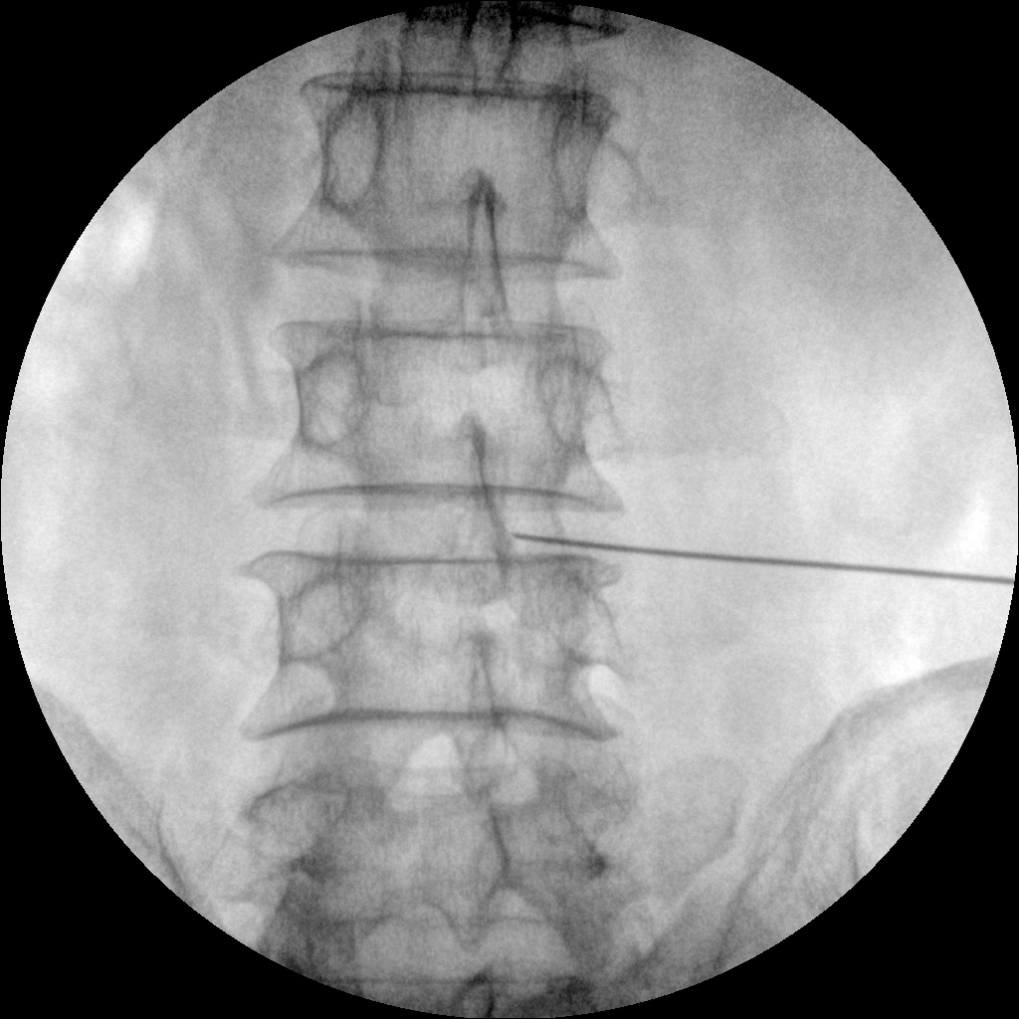

Clinical picture

臨床圖片